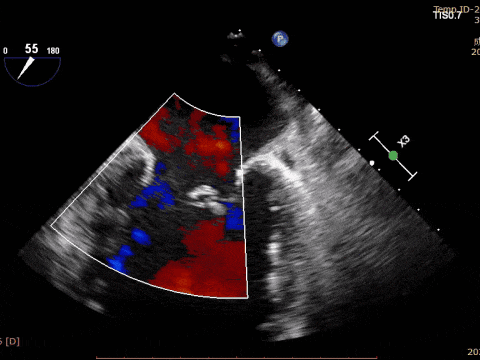

術(shù)前超聲

VFMR,反流2區(qū),新分型CCA型,MR重度(VC:3*14mm),A2:21mm,P2:10-11mm,AP:30mm,前后葉間3mm gap,MVA約5.1cm²